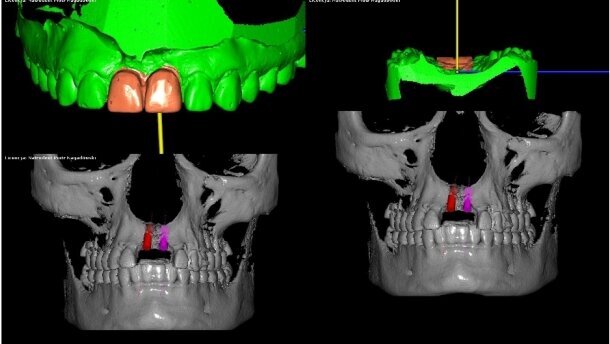

Nie udałoby się takie zakończenie, gdyby nie programy typu DDS-Pro. Jest to oprogramowanie przeznaczone do planowania implantacji, a także zabiegów ortognatycznych z wykorzystaniem tomografii komputerowej oraz skanów modeli laboratoryjnych zapisanych w formacie stl. Pozwala również na wykorzystanie modeli z wax-up do planowania leczenia protetycznego. Co, moim zdaniem, niezwykle ważne, produkt ten powstał w Polsce, zaś jego dystrybucją i wsparciem zajmuje się firma Natrodent z Łodzi.

Wprowadzenie danych do programu odbywa się poprzez import 2 rodzajów plików DICOM z tomografii komputerowej i STL ze skanera laboratoryjnego lub skanera wewnątrzustnego. Tak zaimportowane pliki, po ich nałożeniu na siebie, pozwalają na precyzyjne, dokładne odzwierciedlenie stanu faktycznego jamy ustnej pacjenta z uwzględnieniem układu kostnego oraz stanu zębów i tkanek miękkich. Tomografia komputerowa nie daje 100% dokładnego obrazu śluzówki i zębów, przez co dotychczas wykonywane w oparciu o nią szablony, nie należały do dokładnych i ulubionych przez implantologów. Dodatkowo, znacznie podnosiły koszt zabiegu. DDS-Pro wyeliminował wszystkie te wady – jest to program kompletny.

Konfiguracja programu umożliwia precyzyjne umieszczenie implantu w kości z zachowaniem proporcji pod przyszła pracę protetyczną (kąt wychylenia oraz odległości pomiędzy punktami). Wykorzystane w nim rozwiązania pozwalają na przeprowadzenie przyszłego zabiegu implantacji w taki sposób, jaki zaplanowany został wirtualnie (za pomocą szablonu, który tworzymy). Szablon drukujemy na drukarce 3D lub frezujemy w CNC i tym sposobem uzyskujemy swoisty pozycjoner, który wskaże dokładne położenie implantu zarówno dla uzyskania dobrego efektu kosmetycznego, jak i dla głębokości jego wprowadzenia. Błąd ludzki ograniczamy do minimum. Dla systemów implantologicznych, które w swojej ofercie proponują tuleje prowadzące, szablon implantologiczny wykonywany jest odpowiednio z miejscem na tuleję.